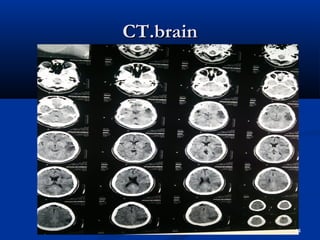

CCTT..bbrraaiinn

44

45

 HHee hhaasslleeuuccooccyyttoossiiss,,  RRaaiisseedd CCRRPP  RRaaiisseedd LLDDHH  UURRIINNEE :: nneepphhrriittiicc ppiiccttuurree  PPlleeuurraall fflluuiidd:: ttrraannssuuddaattiivvee.. (( ttrraannssiieenntt))  BBlloooodd ccuullttuurree :: - vvee  HHCCVV:: ++vvee .. AAuuttooiimmmmuunnee sseerroollooggyy :: -vvee..  AAnnggiiooggrraapphhyy:: nnoorrmmaall  CCTT.. bbrraaiinn,, EECCHHOO,, aanndd DDoopppplleerr II sshhoowweedd yyoouu.. 50